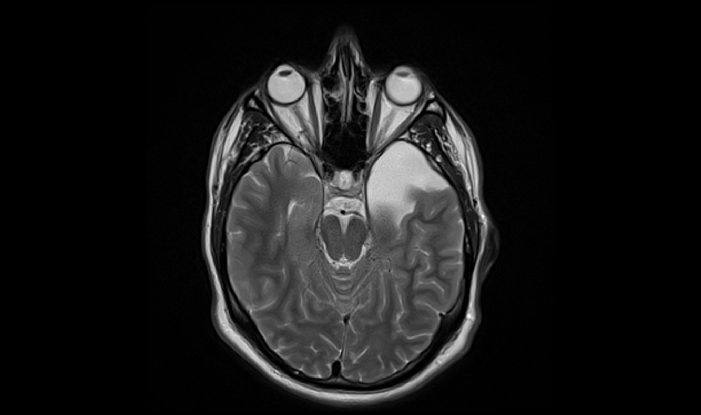

Susan: Bioinformatics. NVIDIA had this really cool demo last year where they took an MRI or something and used machine learning to turn it into a 3D view. You know, automatically segmenting out organs and all sorts of stuff. I mean, this is just like the level one stuff.

An MRI image of a person with an arachnoid cyst in their left, inferior frontal lobe.

Susan: It's amazing. Even without being a doctor you can look at some of the stuff now and say, "That's clearly not supposed to be there, you may want to get that looked at."

Susan: Well, let's talk about you and monitoring you and what you can get out of that. Forget big medicine. Let's not talk about being able to segment the body and find organs and find all sorts of things wrong with you. Let's hook up an AI that monitors you daily, takes your pulse, figures out your heart rate and your respiration and how much you're easting or, what activities you're doing and starts figuring out whether or not you feel good or bad and how to tweak you to get better.

Scott: I think there's some things in the medical side that we didn't talk about like, identifying cancer, or like, being able to go into this imagery a lot better and tell you what's going on. You touched on like three dimensional reconstruction and being able to look at it better but, you can also have areas pointed out to you like, "Well, this looks like a problem."

Susan: This is not your standard kidney. One of the classic things in facial recognition, the first thing you always learn about is using principal component analysis or something along those lines to say, "This is what the standard face looks like" so, recognizing faces and recognizing those things. You can do that with, effectively, a kidney but, with a lot better results as you use much stronger techniques. And, now you walk in for your weekly, your monthly, your yearly exam and, you quickly zip around, do an MRI or whatever technique they're going to use to scan the inside of your body and, poof, areas in you are marked with little highlights. You know, green, yellow, red, black.